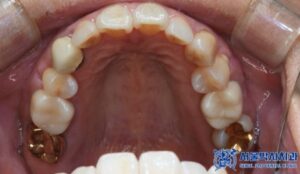

위 환자분은 전체적인 구강 검진을 위해

집 근처에 있는 저희 치과를

방문하셨는데요.

먼저 전체적인 검진 결과,

왼쪽 아래 큰 어금니 부위에서

금 인레이 아래쪽으로 이차 충치와

염증이 발견되었습니다.

문제가 있던 왼쪽 아래 큰 어금니 이외에도

검진을 진행하는 과정에서 오른쪽 송곳니와

왼쪽 아래 작은 어금니에 기존 타 치과에서

시술한 보철물이 있었는데,

시간이 지나면서 일부 변색된 부분이

눈에 띄었습니다.

이는 보철물 주변으로 우식이

진행된 것으로 보였는데요.

치료를 위해 기존 보철물을 제거하고

새로운 크라운으로

교체하기로 하였습니다.